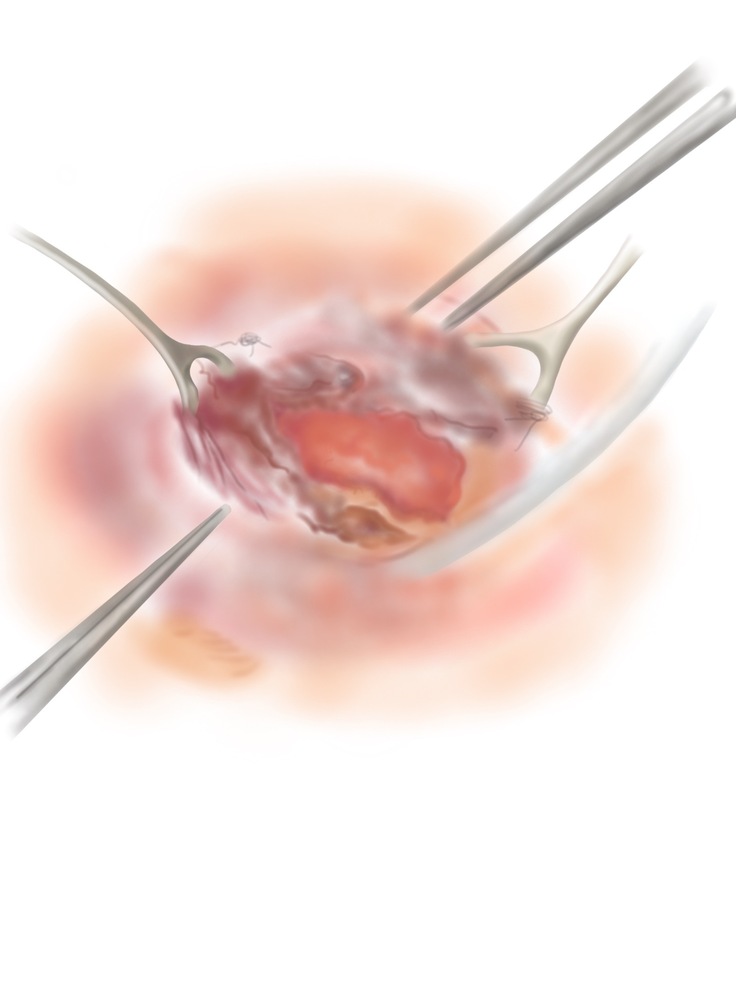

みなさん、お気づきだと思いますが、このプロジェクトの紹介ページには、たくさんのイラストを載せています。お腹の中で病気になっている赤ちゃんの絵なので、見る人に不安やこわさを与えないように、やさしいタッチで描いたイラストを掲載しています。

実は、このイラスト、私たちの仲間で、大阪大学の総合周産期母子医療センターで事務職員として働いているKさんが描いてくれたものなんです。見ていると穏やかになる落ち着いた絵ですよね。しかも、病気のことをできるだけ正確に表現したいので、一度描いてくれた絵を私たちと何度も見直して、正確に表現できるようになるまで根気強く描き直してくれてできたイラストたちなんです。大変思い入れのあるイラストたちです。

この場を借りて、Kさん、ありがとう。これからもよろしくお願いします。